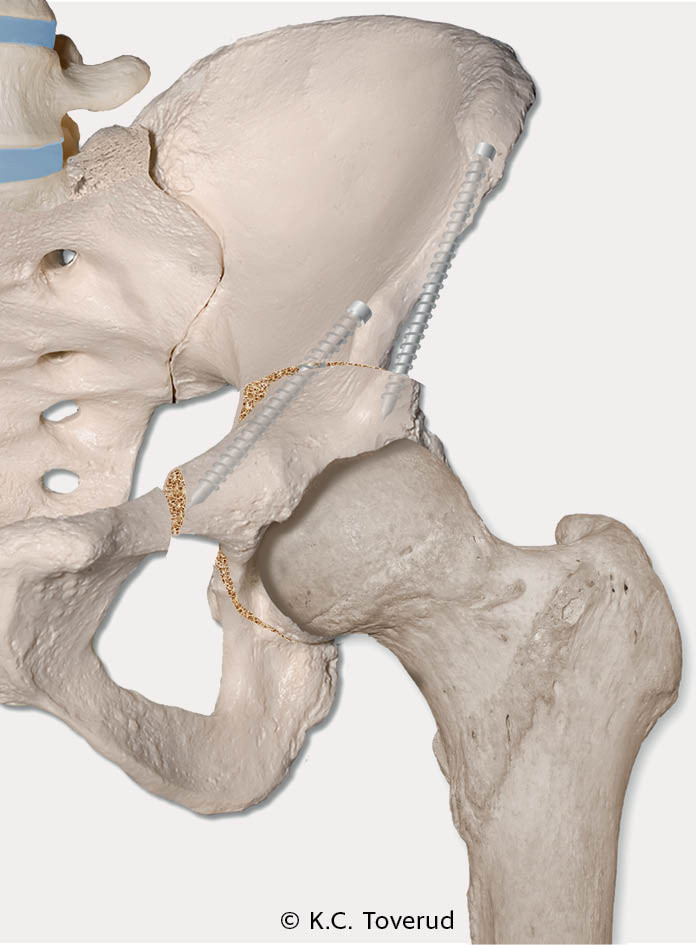

Ved andre hoftelidelser, spesielt hoftedysplasi og subluksasjoner, kan man gjøre bekkenosteotomier for å oppnå god caputdekning og leddstabilitet. Takplastikk, hvor acetabulums dekningsgrad økes ved bentransplantat som ved Spitzys prosedyre (figur 2), er et kirurgisk alternativ hos barn over åtte år (9). Fra 12-årsalderen og hos utvokste pasienter brukes oftest periacetabulær osteotomi (PAO) (10). Prosedyren går ut på reorientering av acetabulum for å gi bedre caputdekning (figur 3).